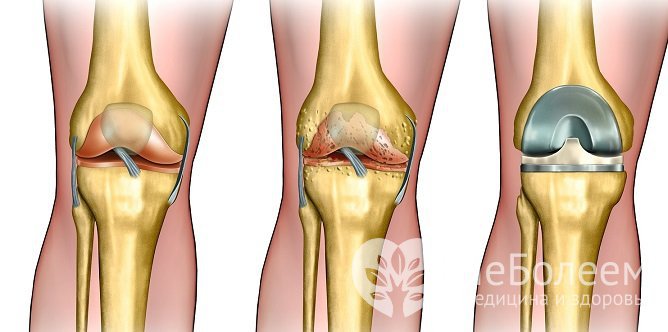

Остеоартроз характеризуется постепенными дегенеративно-дистрофическими изменениями хрящевой тканиТермин остеоартроз (деформирующий остеоартроз, деформирующий артроз, остеоартрит) объединяет группу заболеваний, отличающихся этиологическим фактором, но имеющих сходный патогенез, морфологические изменения и клинический исход.

При недостаточном количестве глюкозамина малейшая нагрузка на матрикс ведет к травмированию, потере амортизирующей функция хряща. Вначале он компенсаторно утолщается, но по мере прогрессирования постепенно истончается, разрыхляется, в нем образуются язвы. Данный прогрессирующий патологический процесс называется остеоартрозом.

Заболевание является следствием нарушения равновесия между образованием нового строительного материала и его разрушением. Мягкий, эластичный хрящ теряет свои свойства, превращаясь в тонкий сухой шероховатый объект.

Околосуставные костные структуры начинают разрастаться, что усугубляет течение процесса, обездвиживая сочленение и приводя к его деформации. Клетки нефункциональной суставной капсулы замещаются клетками соединительной ткани, что приводит к ее фиброзу и асептическому воспалению.

В конечном итоге процесс приводит к тугоподвижности сочленения и образованию контрактур. Пораженный сустав полностью выключается, теряется его двигательная активность, он становится нефункциональным.

При тяжелом течении патологии проводится эндопротезированиеТяжелые, инвалидизирующие коксартрозы и гонартрозы лечатся эндопротезированием – операцией по замене сустава искусственным.